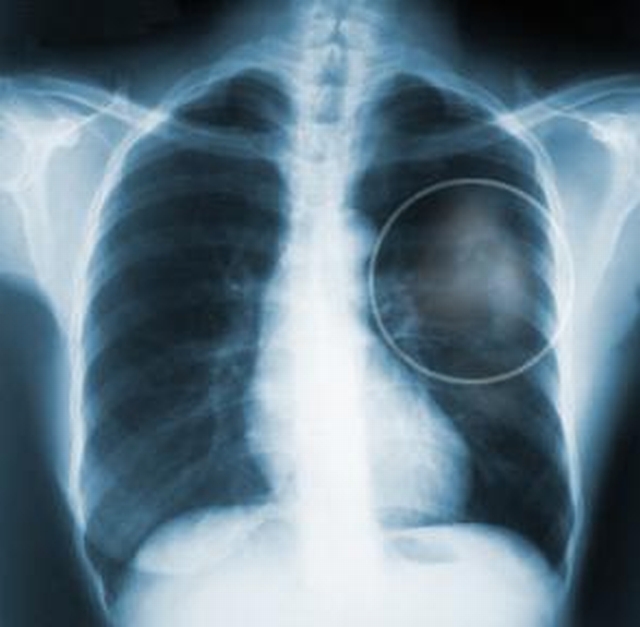

Rusza miejski program profilaktyczny wczesnego wykrywania chorób płuc u kobiet i mężczyzn. Zadanie będzie finansowane z budżetu Miasta Kalisza.

W ramach programu wykonywane będą: badania RTG na podstawie skierowań wystawionych przez lekarzy rodzinnych. Skierowania są przeznaczone tylko dla osób zamieszkałych w Kaliszu z roczników od 1997 i starszych.